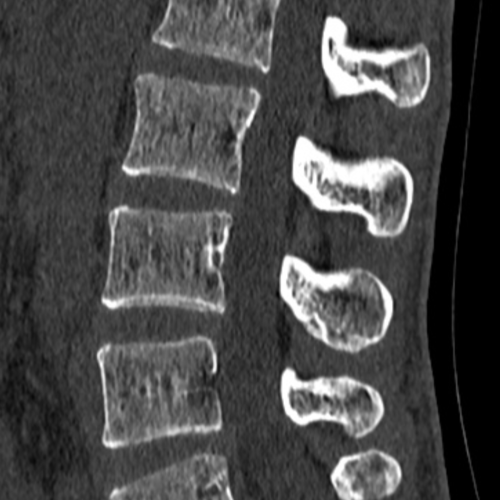

La radio, scanner ou IRM du rachis permet de dépister :

- De l’arthrose rachidienne

- Uncarthrose cervicale avec rétrécissement des trous de conjugaison, responsable de Névralgie Cervico Brachiale (NCB)

- Discarthrose dorsale ou lombaire avec pincements discaux

- Arthrose articulaire postérieure

- un canal lombaire rétréci

- une hernie discale

- une arthrose postérieure

- une lyse isthmique chez les patients sportifs notamment, pouvant générer un spondylolisthésis

- des tassements vertébraux traumatiques ou ostéoporotiques

- des tassements vertébraux secondaires à des métastases osseuses rachidiennes

- des troubles de la statiques avec scoliose (mesure de l’angle de Cobb), cyphose, latéro listhésis dégénératif

Les résultats sont parfois normaux et justifie la réalisation complémentaire d’une IRM cervicale ou une IRM lombaire à la recherche d’une hernie discale conflictuelle avec une racine nerveuse et responsable d’une sciatique, d’une NCB (névralgie cervico-brachiale) ou d’une cruralgie.